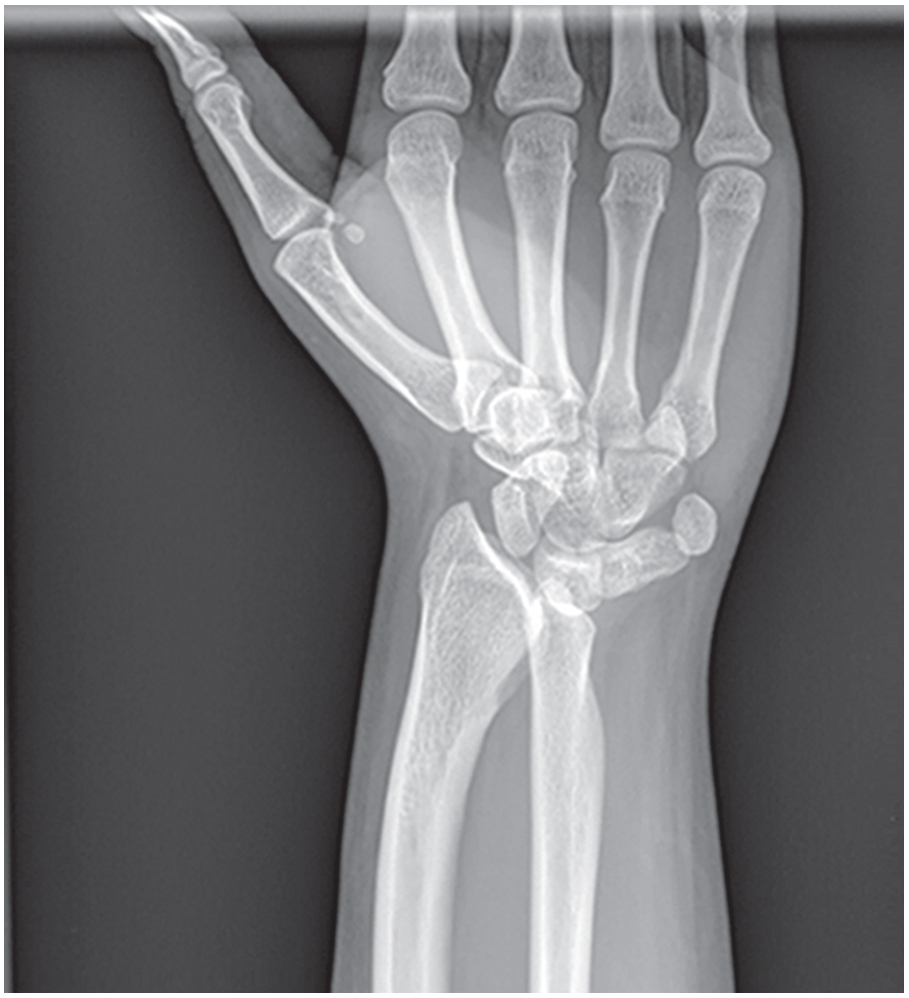

La deformidad de #Madelung afecta a la #muñeca y se caracteriza por las angulaciones radial y palmar de la región distal del #radio. La causa es la detención del crecimiento de los lados palmar y cubital de la metáfisis distal del radio. 📚Nelson. Tratado de pediatría © 2020.